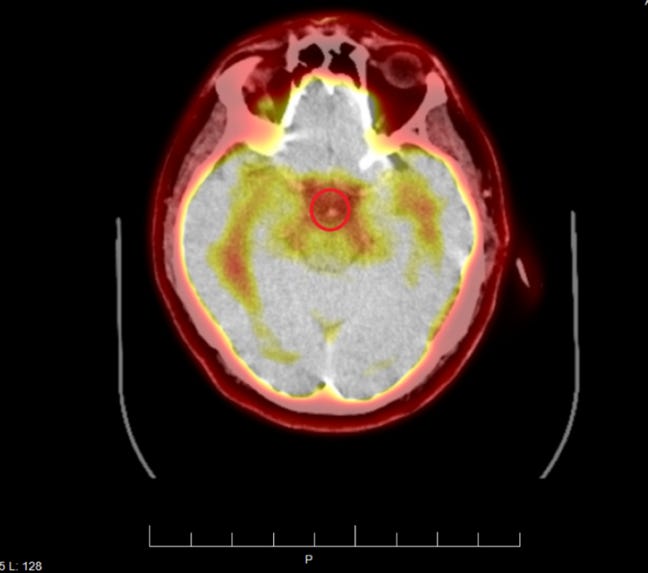

Mon patient a subi plusieurs examens d'imagerie révélant la présence de micropuces implantées. Ces emplacements correspondaient aux zones de torture les plus sévères. Ci-dessous, vous pouvez voir une micropuce entourée :

L'examen TEP cérébral haute définition montre la micropuce au même endroit :